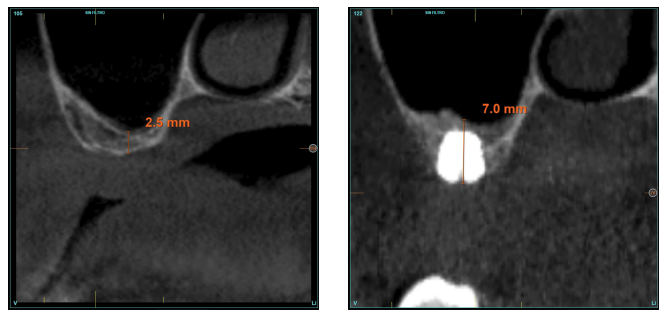

Los pacientes acuden a las revisiones posteriores realizándose un Cone-Beam de control a los 5 meses (antes de la carga del implante) y posteriormente al año de carga, realizándose posteriormente una nueva medición en estas imágenes para analizar la ganancia ósea y el mantenimiento de la misma. En estas revisiones, se recogen datos sobre complicaciones protésicas o pérdidas óseas crestales en estos pacientes, así como posibles fracasos.

La altura media del volumen óseo residual fue de 3,1 mm (+/- 0,3 mm con un rango de 3-4 mm). En todos los casos se realizó una elevación de seno transcrestal, con hueso autólogo particulado obtenido del fresado de la zona de generación del neoalveolo para la inserción del implante, siendo la media de esta elevación sobre el ápice del implante en milímetros de 2,8 mm (+/- 0,99 rango 1,9 -5 mm). En el TAC de control al año de carga de los implantes estudiados, se mantiene la ganancia ósea lograda, no observándose disminución del volumen ganado, únicamente tres casos mostraron una disminución de entre 0,4 y 0,5 mm del volumen inicial al final (Tabla).

En las Figuras 2- 19 se muestra uno de los casos incluidos en el estudio.

la oseointegración del implante 6 meses después de la cirugía. Se observa una ganancia ósea de 4 mm.